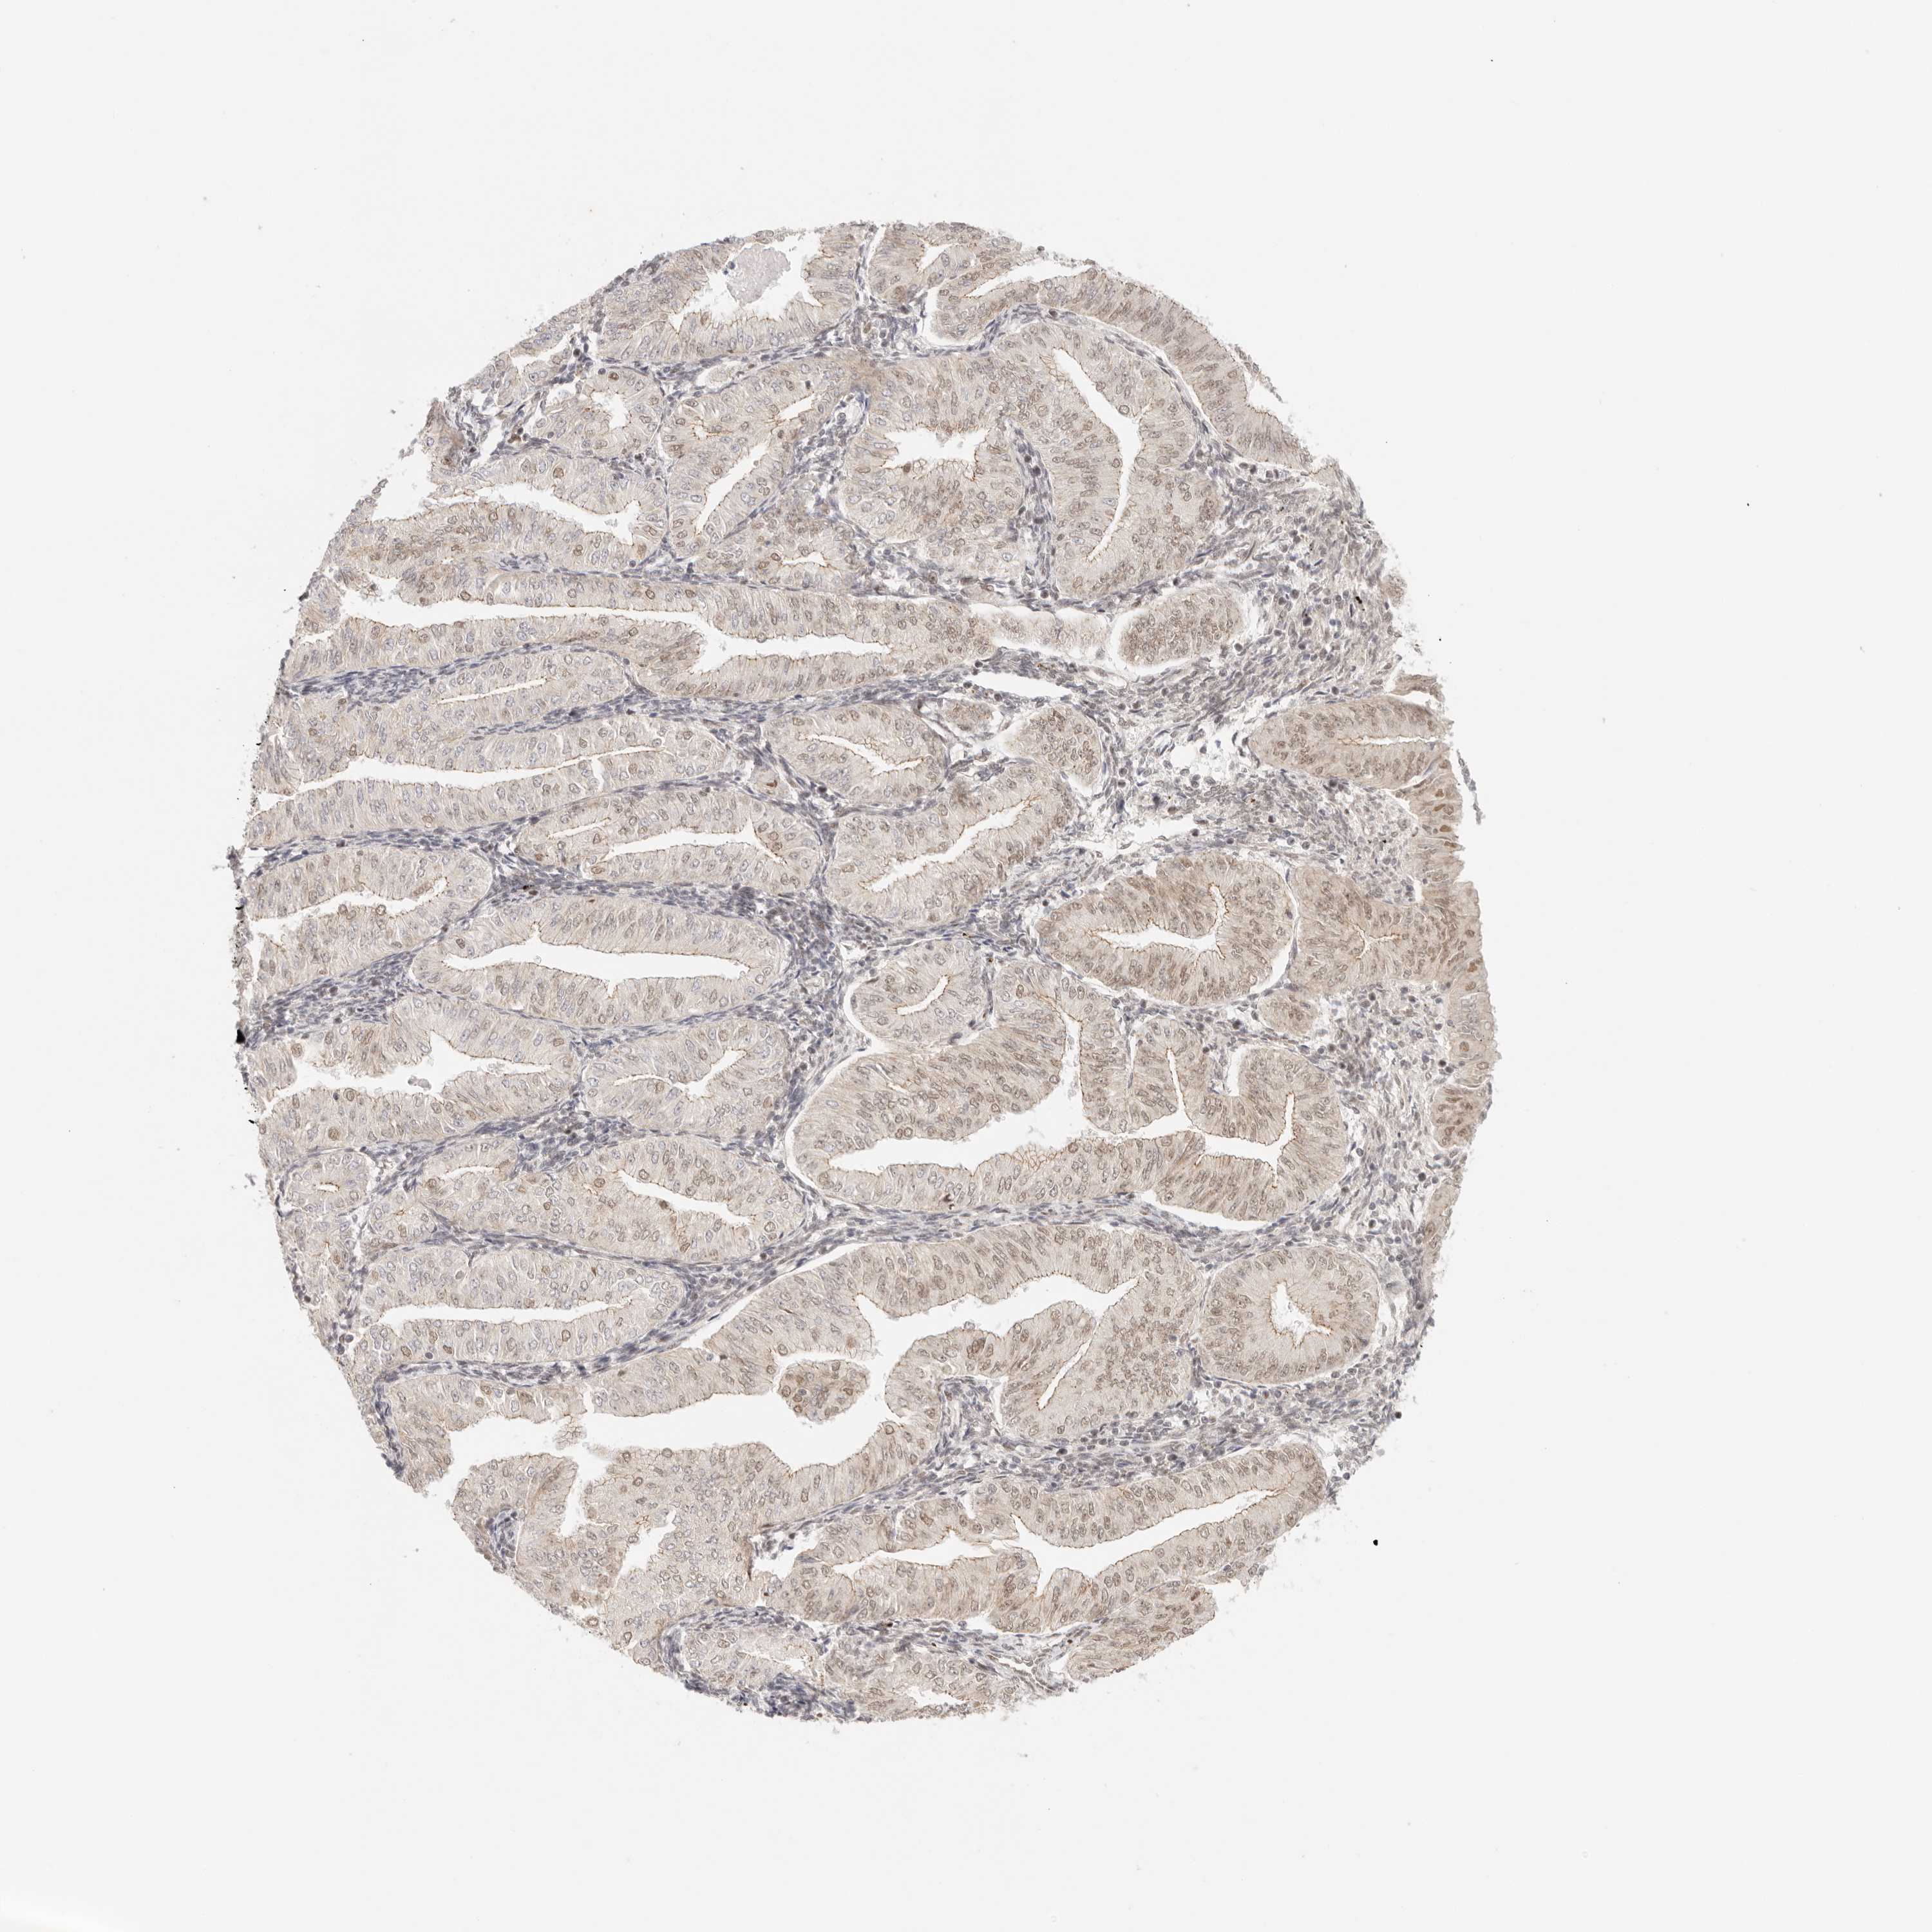

ENDOMETRIAL CANCER - Protein expressioni

A mouse-over function shows sample information and annotation data. Click on an image to view it in a full screen mode. Samples can be filtered based on level of antibody staining by selecting one or several of the following categories: high, medium, low and not detected. The assay and annotation is described here.

Note that samples used for immunohistochemistry by the Human Protein Atlas do not correspond to samples in the TCGA dataset.

Antibody stainingi

Antibody staining in the annotated cell types in the current human tissue is reported as not detected, low, medium, or high, based on conventional immunohistochemistry profiling in selected tissues. This score is based on the combination of the staining intensity and fraction of stained cells.

Each image is clickable and will lead to virtual microscopy that enables deeper exploration of all samples and also displays staining intensity scores, fraction scores and subcellular localization as well as patient and tissue information for each sample.

Antibody HPA026794

Staining

High

Medium

Low

Not detected

Intensity

Strong

Moderate

Weak

Negative

Quantity

>75%

75%-25%

<25%

None

Location

Nuclear

Cytoplasmic/membranous

Cytoplasmic/membranous,nuclear

Adenocarcinoma, NOS

Adenoma, NOS